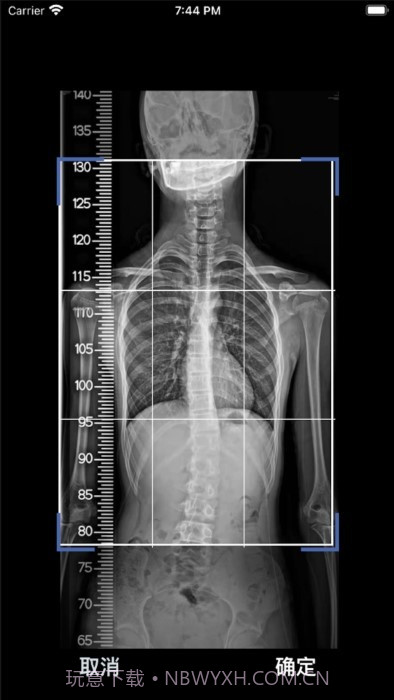

老实说,这款cobb角测量分析平台简直是医生和脊柱侧弯患者的福音!🌟 通过智能测量功能,能够迅速获取cobb角,准确率高得让人放心。对于有脊柱健康需求的小伙伴们来说,了解自己的状况特别重要,不仅能省时省力,更能随时存储和导出数据,后续分析也是轻松搞定!总之,这款应用为提高医疗效率、帮助患者掌握健康状况提供了强有力的支持,真心推荐给大家!

自动识别和标记椎骨,精准度高达95%,真是放心!

智能测量功能超赞,帮你快速获取cobb角,省时省力!